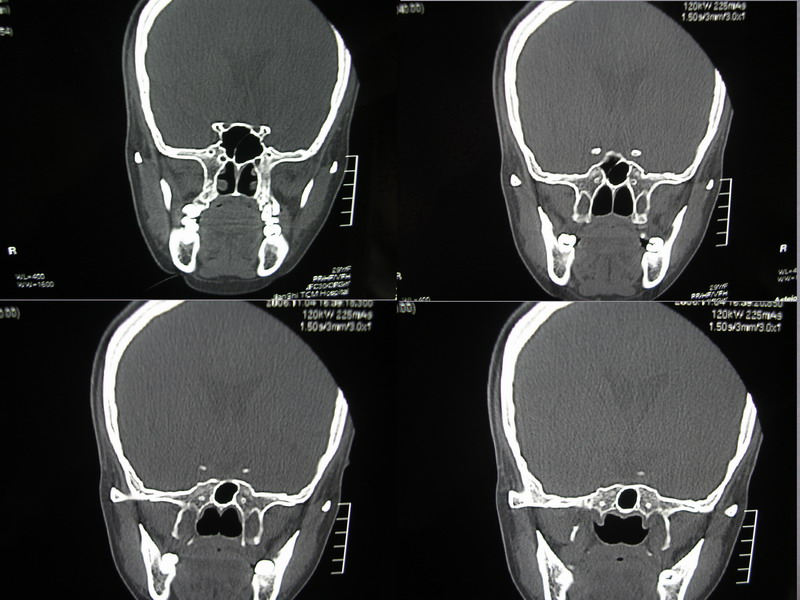

标题: CT5147:头颅,请大家看看

向××,女,29岁,二十天前高热,抗炎治疗后双眼斜视,肌无力,双下肢张力ii级。

双下肢无力,芦脑看没有什么问题?回不回是腰椎的问题呀/

可能是因为图片太小了,总感觉左侧颞叶和右侧额叶前部看的不是很舒服。